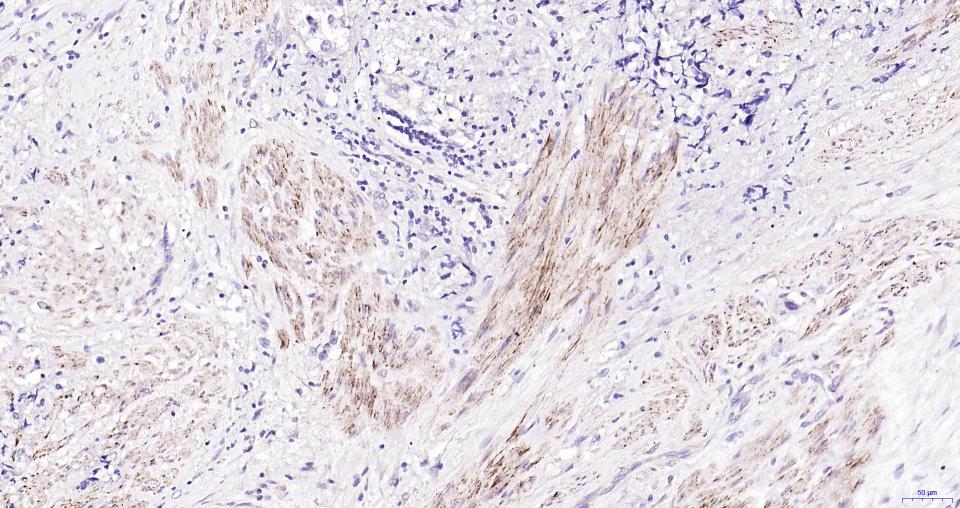

细胞粘附蛋白(Call Adhesion Protein) 神经元标志物 NCAM-1为神经细胞粘附分子,主要分布于神经组织,神经—肌肉接头,神经—内分泌腺和某些内分泌腺以及大多数神经外胚层来源的细胞、组织和肿瘤中。 NCAM 1主要用于视网膜母细胞瘤、髓母细胞瘤、星形细胞瘤、神经母细胞瘤等肿瘤方面的研究。CD56(神经细胞黏附分子,NCAM)表达于大部分神经外胚层来源的细胞系、组织和肿瘤如视网膜母细胞瘤、成神经管细胞瘤、星形细胞瘤以及成神经细胞瘤。它也表达于一些中胚层来源的肿瘤如横纹肌肉瘤。NK细胞以及NK细胞淋巴瘤为阳性。CD56被认为是NK细胞肿瘤的重要标志物。该抗体识别分子量为180,145和125kDa亚型。